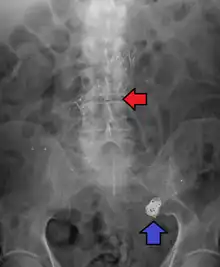

Abdominal aortic aneurysms are commonly divided according to their size and symptomatology. An aneurysm is usually defined as an outer aortic diameter over 3 cm (normal diameter of the aorta is around 2 cm),[37] or more than 50% of normal diameter that of a healthy individual of the same sex and age.[10][38] If the outer diameter exceeds 5.5 cm, the aneurysm is considered to be large.[36]

Endovascular coiling was introduced by Italian neurosurgeon Guido Guglielmi at UCLA in 1989. It consists of passing a catheter into the femoral artery in the groin, through the aorta, into the brain arteries, and finally into the aneurysm itself. Platinum coils initiate a clotting reaction within the aneurysm that, if successful, fills the aneurysm dome and prevents its rupture.[42] A flow diverter can be used, but risks complications.[43]